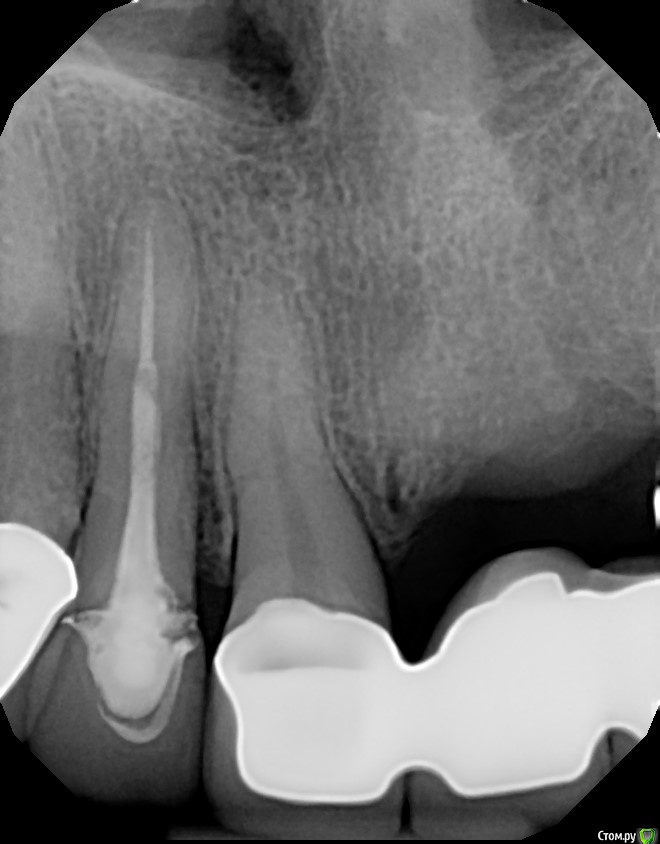

Dirina12 Опубликовано 11 июля, 2017 Поделиться Опубликовано 11 июля, 2017 Чтобы сохранить зуб предлагают делать операцию (endodontic surgery) потому что там соит пост (штифт) и если лечить через зуб то от зуба ничего не останется и не на что будет прикрепить коронку.. Поможет ли это и стоит ли делать?Зуб номер 7 ( маленький отдельный зуб) Ссылка на комментарий

Dirina12 Опубликовано 11 июля, 2017 Автор Поделиться Опубликовано 11 июля, 2017 А по какому поводу операция?Что беспокоит?Зуб чувствительный, и боль проходит вверь сквозь синус в голову. Наверное кариес между зубом и коронкой. Ссылка на комментарий